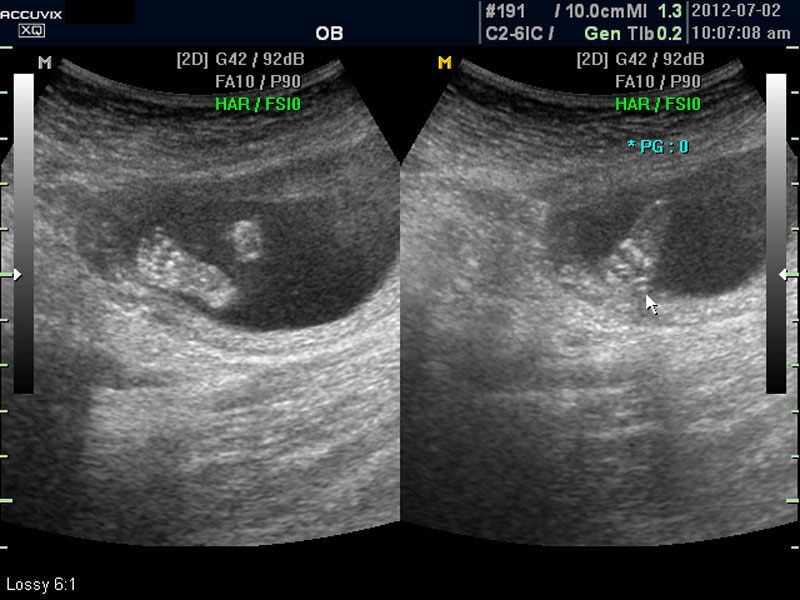

따라서 부분 부분 살펴 보면서 해당 모습을 찍어서 저장하거나 인쇄하여 드리기도 하는 것이며 아래 사진은 태아의 다리 부분을 찍은 것입니다.

양수의 양은 태아의 건강과 관련된 지표로 너무 많거나 너무 적으면 좋지 않은데 그 절대양을 측정할 수는 없어서 양수가 많은 부분의 깊이를 측정하거나 혹은 개략적으로 전체에서 차지하는 부분을 봐서 이상 여부를 판단합니다.

사진에서 검게 보이는 것이 양수입니다. 양수에 대하여는 색깔이나 밀도 등 다른 요소는 알기 어려워서 그 양만 가지고 판단을 하게 됩니다.

임신 초기나 중기의 양수 이상 중에는  대체로 태아의 건강 이상으로 인한 양소 과소증이 더 많은 편입니다.